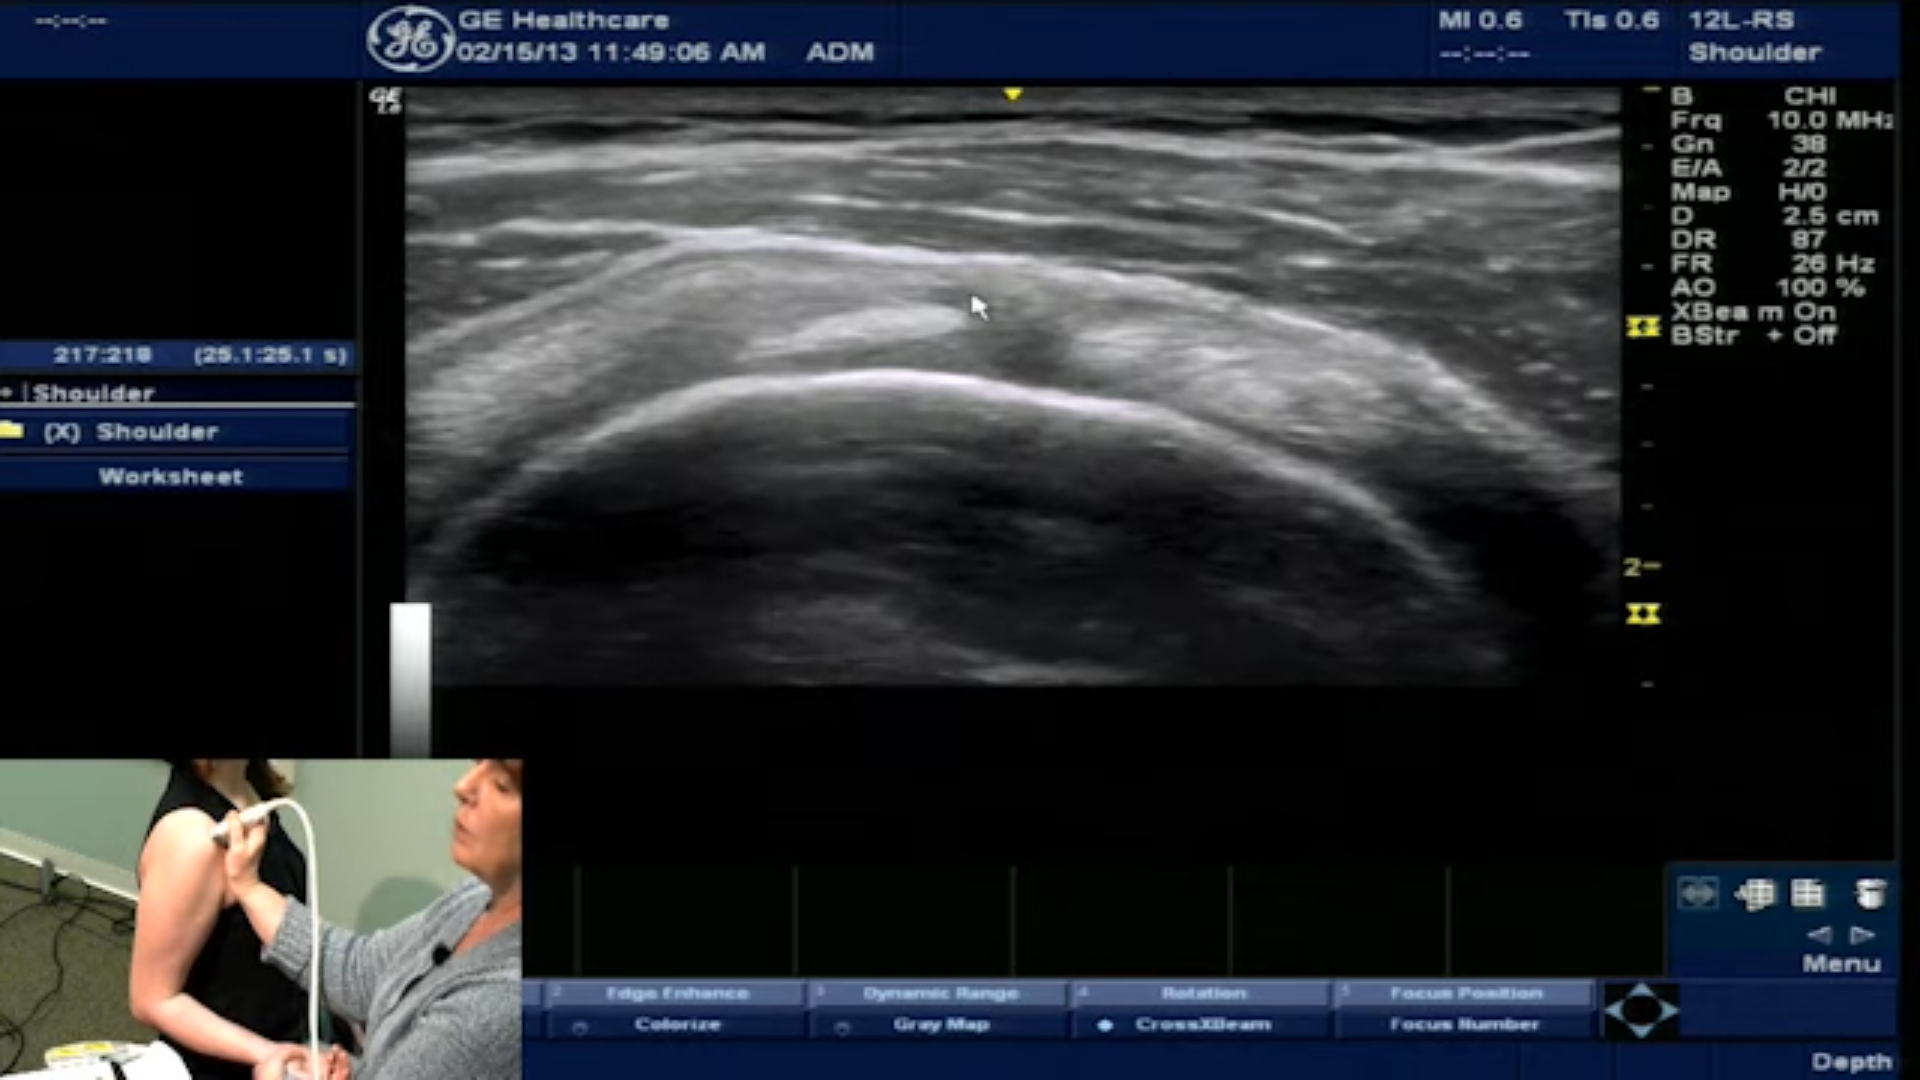

With the shoulder in this position, you’ll be able to see the main components of the rotator cuff interval. Begin by identifying the subscapularis tendon at the forefront. Right beside it, the biceps tendon becomes more defined. You’ll also spot the supraspinatus tendon and, just above it, the coracohumeral ligament.

Each of these structures has a distinct ultrasound appearance. Becoming familiar with these visuals will not only improve diagnostic precision but also facilitate communication with patients when explaining shoulder anatomy and potential injuries.